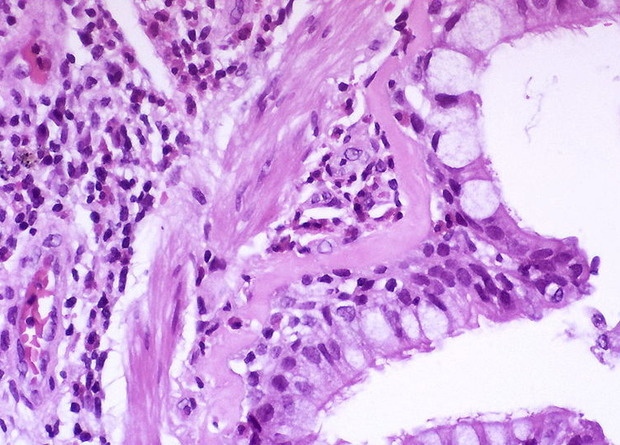

Вакцина от аллергической астмы показала свою эффективность при применении на мышах: она уменьшила продукцию эозинофилов, иммуноглобулина E и мокроты в легких, а антитела выявлялись у 60 процентов мышей через год после вакцинации. Об успешном окончании экспериментов авторы сообщили в Nature Communications.

При контакте с аллергеном в дыхательных путях больного астмой продуцируются иммуноглобулин IgE и интерлейкины 4 и 13 (IL-4 и IL-13). Это приводит к каскаду реакций, характеризующихся продукцией слизи и повышенным содержанием эозинофилов в тканях. Антитела, блокирующие